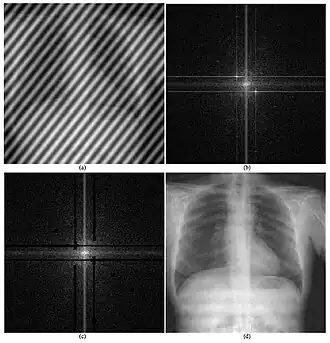

- elaborazione ed analisi di biosegnali e bioimmagini;

Elaborazione del segnale medico

Un'importante applicazione dell'ingegneria dell'informazione in medicina è l'elaborazione dei segnali medici. Si riferisce alla generazione, all'analisi e all'uso di segnali, che potrebbero assumere molte forme come immagine, suono, elettrica o biologica.

Calcolo delle immagini mediche e informatica delle immagini

L'informatica per immagini[46] e l'elaborazione di immagini mediche (Medical image computing - MIC)[47] sviluppa metodi computazionali e matematici per la risoluzione di problemi relativi alle immagini mediche e al loro utilizzo per la ricerca biomedica e l'assistenza clinica. Questi campi mirano a estrarre informazioni o conoscenze clinicamente rilevanti dalle immagini mediche e dall'analisi computazionale delle immagini. I metodi possono essere raggruppati in diverse grandi categorie: segmentazione dell'immagine, registrazione dell'immagine, modellazione fisiologica basata sull'immagine e altri.